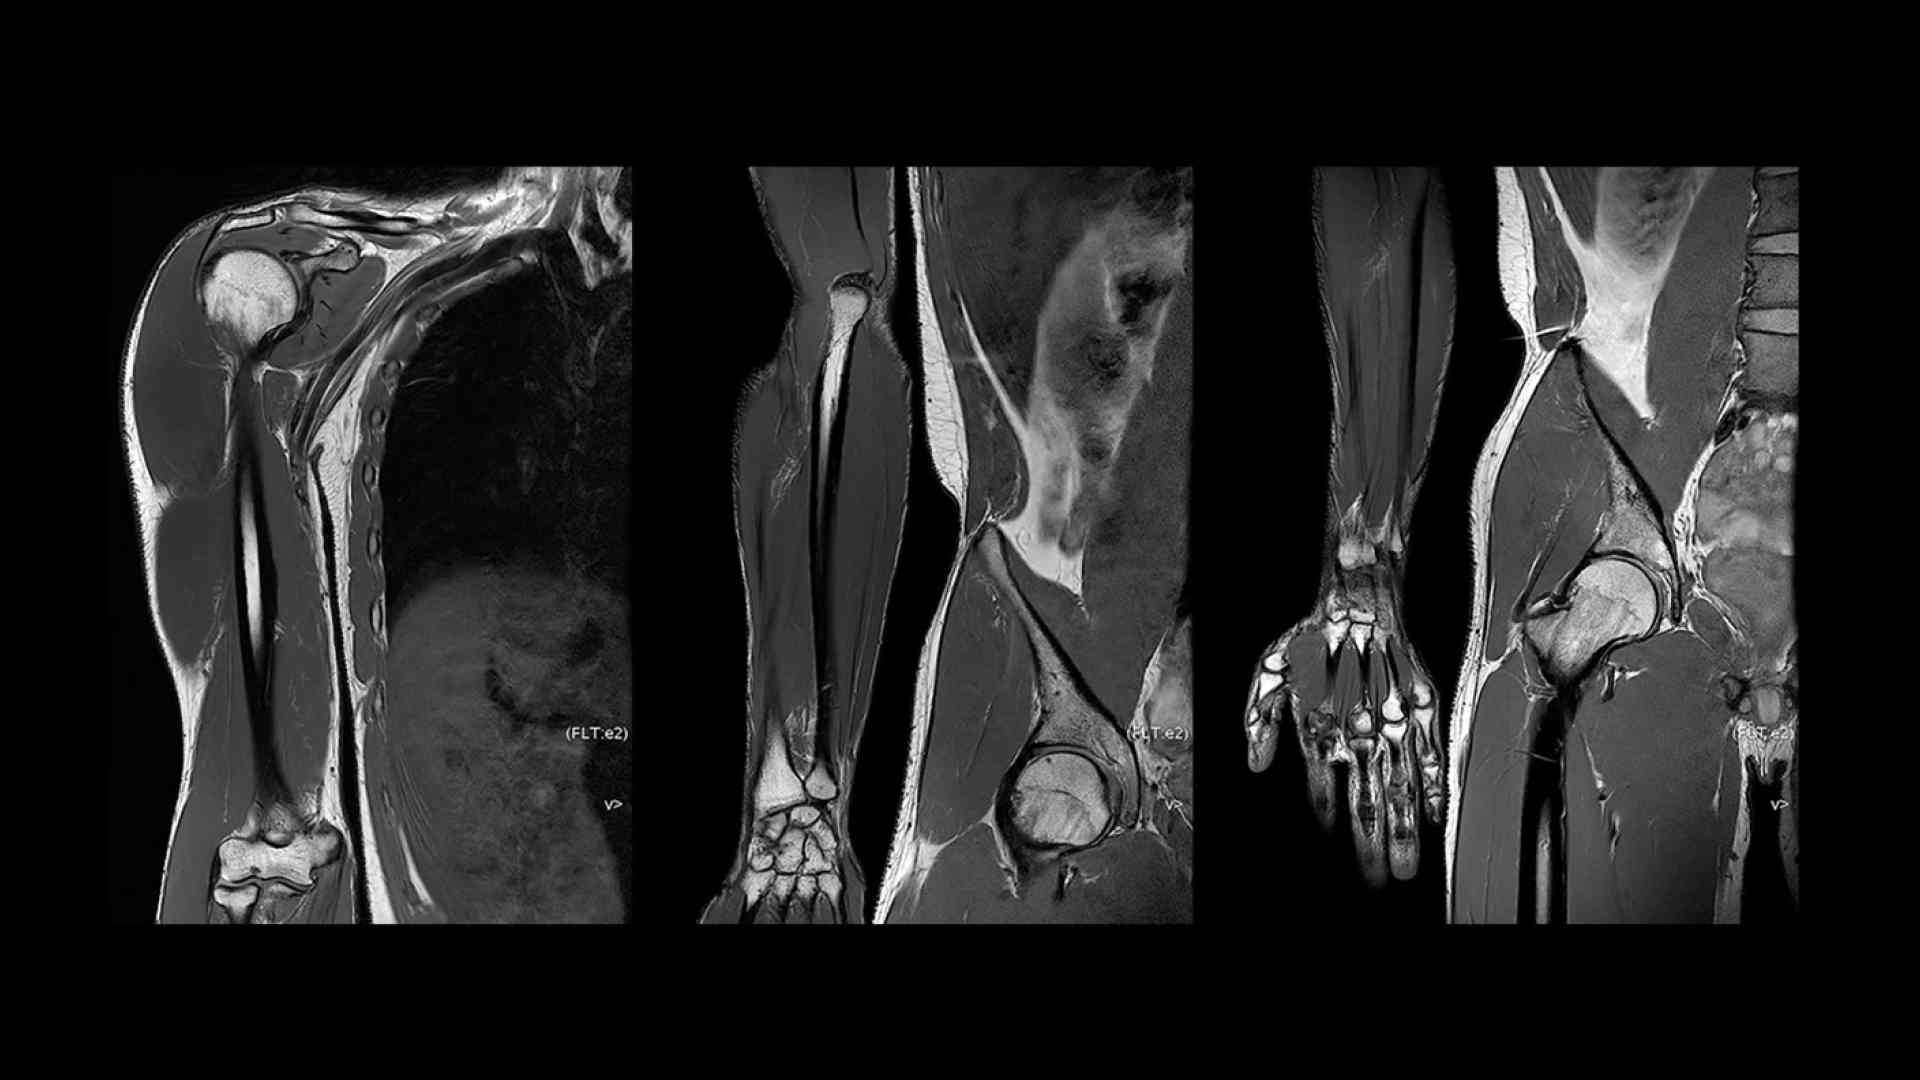

Clinical confidence

Revolutionary, deep-learning-based reconstruction techniques such as AIR™ Recon DL provide sharper, clearer, and accurate images